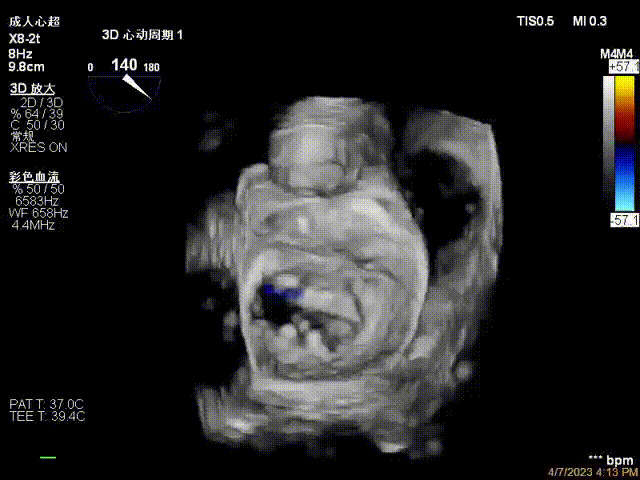

術(shù)前超聲提示二尖瓣重度反流